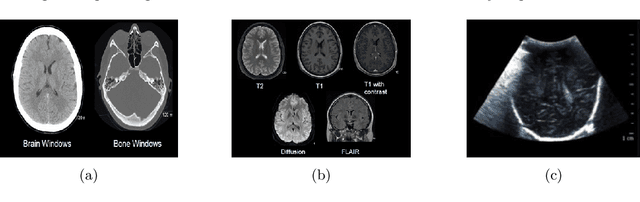

Abstract:The application of machine learning to radiological images is an increasingly active research area that is expected to grow in the next five to ten years. Recent advances in machine learning have the potential to recognize and classify complex patterns from different radiological imaging modalities such as x-rays, computed tomography, magnetic resonance imaging and positron emission tomography imaging. In many applications, machine learning based systems have shown comparable performance to human decision-making. The applications of machine learning are the key ingredients of future clinical decision making and monitoring systems. This review covers the fundamental concepts behind various machine learning techniques and their applications in several radiological imaging areas, such as medical image segmentation, brain function studies and neurological disease diagnosis, as well as computer-aided systems, image registration, and content-based image retrieval systems. Synchronistically, we will briefly discuss current challenges and future directions regarding the application of machine learning in radiological imaging. By giving insight on how take advantage of machine learning powered applications, we expect that clinicians can prevent and diagnose diseases more accurately and efficiently.